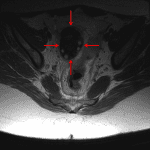

- Enlarged right ovary with peripheralization of ovarian follicles and hypoenhancement of the ovary on postcontrast images

- Ovarian torsion

Enlarged right ovary with peripheralization of ovarian follicles and hypoenhancement of the ovary on postcontrast images, concerning for ovarian torsion. Recommend urgent pelvic ultrasound for further assessment.